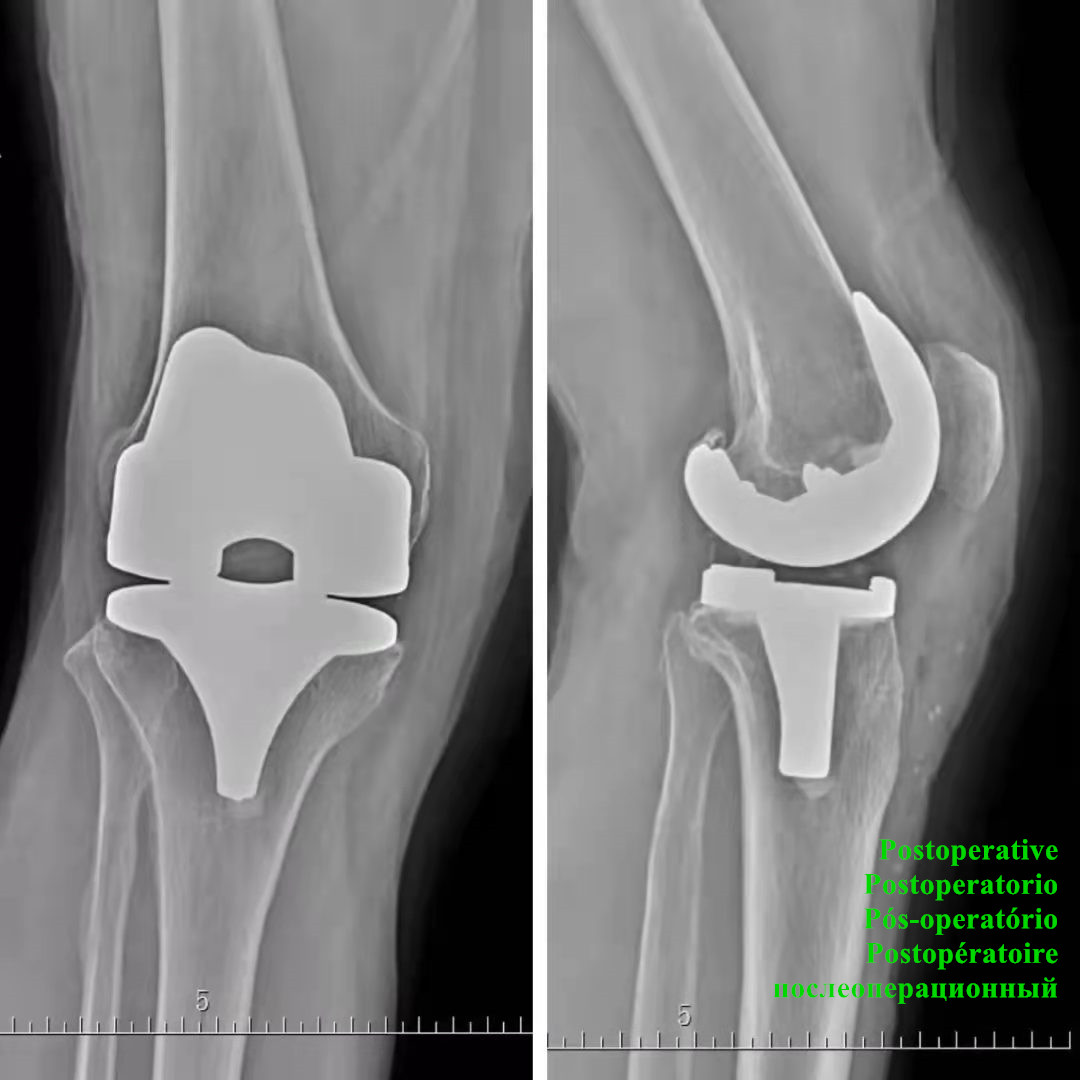

Artificial implants made to relieve knee joint pain, restore knee joint structure and function, and correct joint deformities.